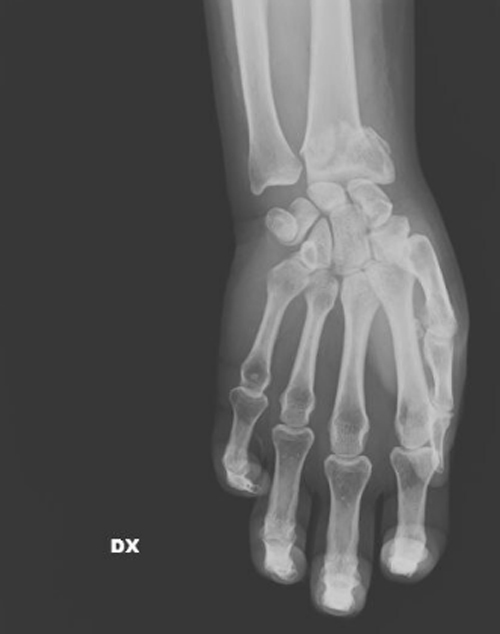

Με την ευκαιρία αυτή, στο μιλανέζικο νοσοκομείο Σαν Κάρλο και με πρωτοβουλία της ιατρού Μαρία Γκράτσια Βανταντόρι, 59 ετών, χειρουργού επί 26 χρόνια εκεί, γίνεται έκθεση ακτινογραφιών γυναικών οι οποίες προσήλθαν στο νοσοκομείο κατόπιν σοβαρού τραυματισμού τους. Οι ακτινογραφίες, λέει η ιατρός στη ρεπόρτερ της La Repubblica, δείχνουν την οικογενειακή βία που υφίστανται οι γυναίκες.

«Εδώ είναι η καθημερινή φρίκη που αντικρίζουμε στα έκτακτα περιστατικά. Συχνά οι τραυματισμένες γυναίκες δεν έχουν τη δύναμη να πουν τι τους έχει συμβεί, αλλά τα σώματά τους και τα τραύματά τους μιλούν από μόνα τους». Η ιατρός περιγράφει τα συνήθη: «Σπασμένα οστά σε μύτη, χέρια, πόδια, πληγές από μαχαιριές, εγκαύματα, μελανιές και άλλα σημάδια στραγγαλισμού». Αλλά και τα ασυνήθη: «Μέχρι και με ένα μαχαίρι καρφωμένο στην πλάτη της μας ήρθε μια γυναίκα».

Ετσι η Βανταντόρι αποφάσισε να εκθέσει «εικόνες από έναν αόρατο πόλεμο που διεξάγεται καθημερινώς πίσω από τους τοίχους των σπιτιών», δηλαδή τις ανώνυμες ακτινογραφίες οι οποίες δείχνουν τα βασανιστήρια που υπέστησαν οι γυναίκες «από συζύγους, πρώην συζύγους, συντρόφους». Η ρεπόρτερ του ιταλικού φύλλου χαρακτηρίζει την έκθεση «ακραία και τραγική».